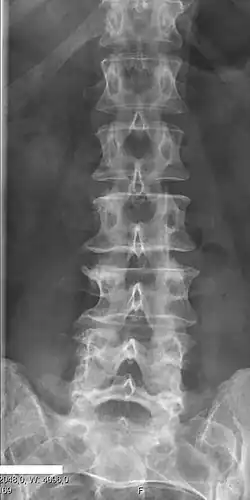

Short ribs at the first lumbar vertebra, which is thus a transitional vertebra, since lumbar vertebrae normally do not have ribs attached to them.

Transitional vertebrae have the characteristics of two types of vertebra. The condition usually involves the vertebral arch or transverse processes. It occurs at the cervicothoracic, thoracolumbar, or lumbosacral junction. For instance, the transverse process of the last cervical vertebra may resemble a rib. A transitional vertebra at the lumbosacral junction can cause arthritis, disk changes, or thecal sac compression. Back pain associated with lumbosacral transitional vertebrae (LSTV) is known as Bertolotti's syndrome. One study found that male German Shepherd Dogs with a lumbosacral transitional vertebra are at greater risk for cauda equina syndrome, which can cause rear limb weakness and incontinence.[11]